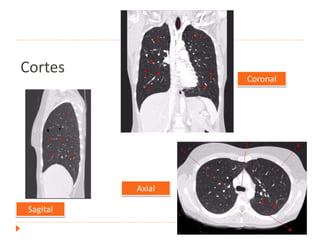

Tomografía de tórax

Cortes

Coronal

Sagital

Axial